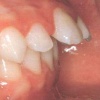

prognaatne hambumus, ülemised eeshambad on ettepoole alumiste suhtes ja eest

progeenne hambumus; alumised eeshambad on ettepoole ülemiste suhtes;

lahihambumus, kui kontaktis on ainult molaarid ehk tagahambad

peetunud lõike- või silmahambad; hambad on küll olemas kuid nad on peetunud

kui puudub lõike- või silmahammas või rohkem kui üks hammas lõualuu ühel poolel